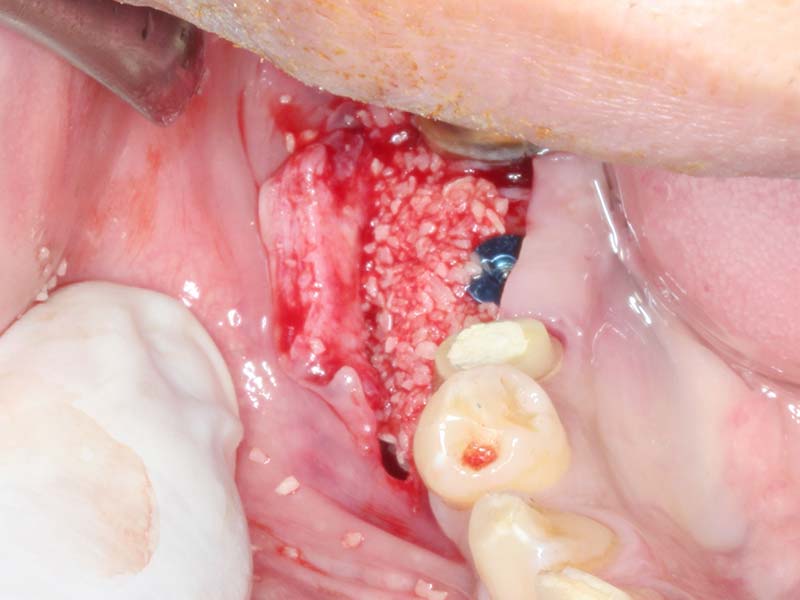

組織增生 首頁 案例分享 組織增生 組織增生 組織增生 缺牙過久,導致組織塌陷 植牙同時合併使用骨粉促進骨頭再生 植牙同時合併使用膠原蛋白,促進牙齦再生 組織穩定後再使用人工皮再增進角化牙齦 Before After 達到理想的組織增生再造